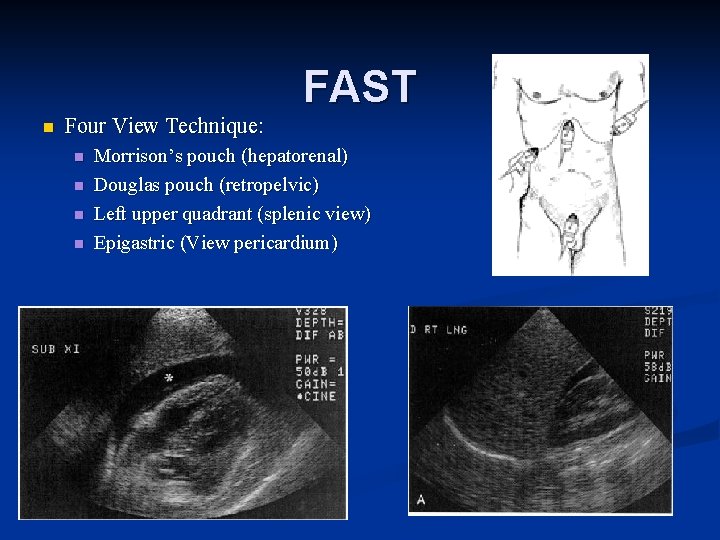

FAST n Four View Technique: n n Morrison’s pouch (hepatorenal) Douglas pouch (retropelvic) Left upper quadrant (splenic view) Epigastric (View pericardium)